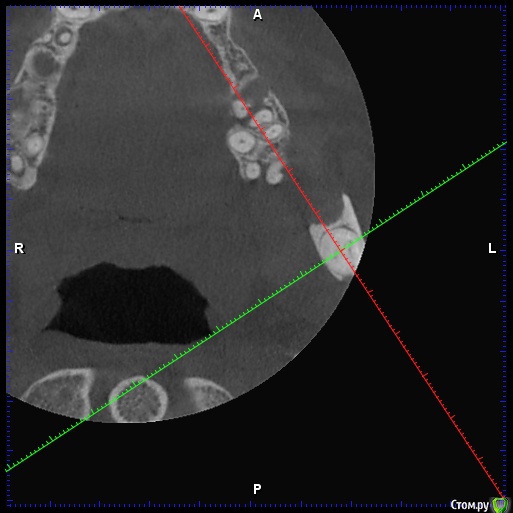

DenisV Опубликовано 18 декабря, 2019 Поделиться Опубликовано 18 декабря, 2019 Уважаемые коллеги, реферативный пациент, после химиотерапии окончил прохождение 2 месяца назад, хочет санировать полость рта (онколог разрешил), обнаружили образование на КТ в ретромолярной области слева. Какое Ваше мнение ? Направить к онкологу? Ссылка на комментарий

Lodkin666 Опубликовано 19 декабря, 2019 Поделиться Опубликовано 19 декабря, 2019 Мне кажется это похоже на сверхкомплектный зуб. Ссылка на комментарий

DenisV Опубликовано 19 декабря, 2019 Автор Поделиться Опубликовано 19 декабря, 2019 Мне кажется это похоже на сверхкомплектный зуб.неоднородной плотности, напрятали это зуб Ссылка на комментарий

Jurai Опубликовано 22 декабря, 2019 Поделиться Опубликовано 22 декабря, 2019 кажется, что зачаток сверхкомплектного или одонтома. Узнайте у пациента нет ли у него снимков прошлых лет - сравнить со свежим. Ссылка на комментарий

Irouil Опубликовано 22 декабря, 2019 Поделиться Опубликовано 22 декабря, 2019 Согласен, похоже на одонтому, чёткая капсула, плотность дентина 2 Ссылка на комментарий